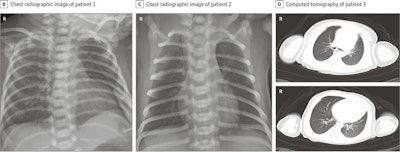

Among 33 newborns, three were diagnosed with COVID-19, as confirmed by RT-PCR testing and either x-ray or CT.

The first two newborns confirmed to have SARS-CoV-2 infection were born at around week 40 of gestation. Both infants had lethargy and fever on their second day of life, with chest x-rays showing pneumonia. Their RT-PCR tests were positive for SARS-CoV-2 on days 2 and 4 and negative on day 6.

The third newborn with COVID-19 was born after 31 weeks and two days of gestation. Chest CT showed pneumonia and neonatal respiratory distress syndrome, which resolved on day 14 after appropriate treatment. RT-PCR tests were positive for SARS-CoV-2 on days 2 and 4 and negative on day 7. The patient also had sepsis and required resuscitation after birth.